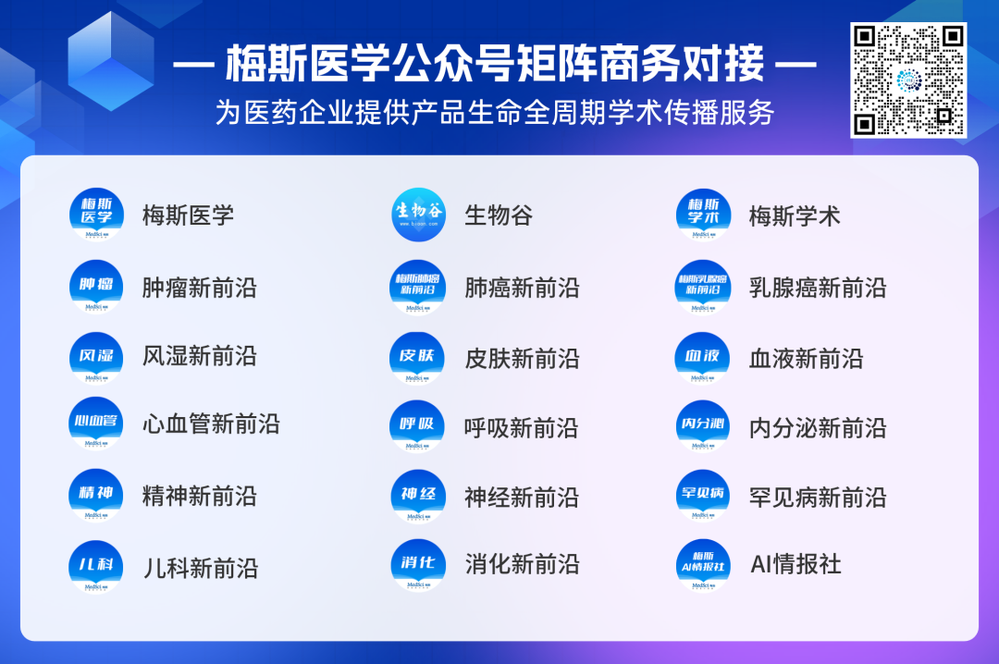

肺磨玻璃结节随访观察了近4年,当地医生说有变化,动员我做手术切除,我想把这几年的C T电子胶片发给伍主任,请你诊断一下。是继续观察还是需要手术切除,右肺上页的两个结节能一次性切除吗?位置比较深能否保留尽量大的肺组织。

方形的是25年的,红色的主病灶,磨玻璃密度伴少许略偏高点密度,但还说不上典型混合磨玻璃病灶,考虑原位癌或微浸润性腺癌可能性大;蓝色的轮廓与边界欠清,位置靠上叶中央,无法段切或楔切;黄色的多发均淡而纯,分布在两肺。圆形粉色的是主要的两处23年时的样子,对比说不上很明显进展。鉴于若手术得切肺叶,何况两肺他处仍的结节,年纪又74了。我倾向保守点,先6-9个月复查,等进展并风险增加再来考虑怎么办的事。意见供参考!

结友担心结节会短期内突然进展,我当时还告诉他不至于的:

我的想法是主病灶在右上叶,且多发,而且位置较深,若手术很可能要切且叶,虽考虑是肿瘤范畴的,但由于不管病灶A还是病灶B均仍是磨玻璃密度,没有纵隔窗可见的实性成分,在两肺多发病灶的情况下,适当保守点再随访下,待有进展并风险增高再干预也不至于影响预后。而且根据既往经验,磨玻璃密度的肺癌基本太会短时间内快速进展。

病灶B似乎灶内有少许密度略偏高,但瘤肺边界欠清晰,总体说不上太显著的进展。

当时结友自己还觉得有点实性成分,血管感觉也有增粗。而我觉得整体密度仍是磨玻璃,轻微的变化仍不足以影响临床决策的程度。

先回顾此前的影像及细节:

病灶没有确切纵隔窗可见的实性成分,但与血管关系较为密切。

这是较为少见的一个病例,磨玻璃为主,而且一直瘤肺边界欠清晰的病灶何以会在之前三年均极缓慢微小变化的情况下,近半年却快速进展呢?从影像细节上看,我们能否进一步分析哪种纯磨玻璃结节可能会较快进展?结合本例,我个人的考虑是:1、病灶整体显得是磨玻璃密度,但灶内并不均匀,就如磨玻璃密度中混入细沙状;2、整体轮廓虽然较清但瘤肺边界相对来说却并不太清晰;3、邻近有血管紧挨,而且与病灶这间缺乏间隙;4、病灶密度不高,没有明显实性成分,却有灶内有细支气管通气征,说明肿瘤成分具有收缩力,却与纯磨的收缩不匹配(纯磨一般不太会有明显收缩力)。如果有上面这些特征可能要提高警惕,一是适当较短的随访间隔,二是影像细节变化要更加注意,开始变化意味着已经进入发展期,而非蛰伏期。当然是否在2025年9月时定得手术了?如果是孤立性的病灶B,且位置位于能简单楔形切除的位置,那是可以考虑的。但位置深、两肺多发,切除范围不小,再今年据肺癌诊疗指南中说的混合磨玻璃结节实性成分不足25%是非侵袭性病变,且几乎不会转移,那么按原则仍再随访显然是可以的。本例的随访变化再次表明磨玻璃密度肺癌的诊疗个体化之路仍是很漫长的,按指南原则的随访或诊疗显然不足以覆盖所有病例,总结与经验积累永远在路上。